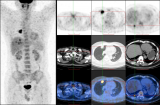

本次读片会的3个病例均为肺内病变的18F-FDG PET/CT影像病例,分别由北京大学第一医院的廖栩鹤医师及北京大学国际医院的宋娟娟医师提供。 2022-07-28 PET/CT靶向治疗

通过在功能成像中增加解剖成像的精度,它在整个疾病过程中的初始诊断、评估、治疗、预后、监测和复发方面构成了重大进步。PET-CT 是 Positron Emission Tomography – 计算机断层扫描的首字母缩写,它是一种核医学设备,包含 PET 扫描仪和 CT 扫描仪,用于获取多个连续视图以创建身体的 3D 图像。 2022-07-28 PET/CT放射性药物